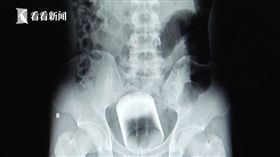

玻璃杯卡肛門2天!已婚男半夜急就醫

怎麼滑進去的?大陸廣州有一名31歲已婚男子到醫院就診...

2017/09/03 10:20